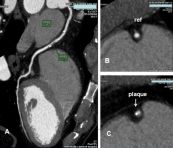

Quét tim có thể cho thấy có nguy cơ cao có một cơn đau tim hoặc các vấn đề khác trước khi có bất kỳ triệu chứng rõ ràng của bệnh tim. Dưới đây là một số thông tin liên quan đến chụp CT scan mạch vành, mời các bạn tham khảo.

Trong chụp mạch CT, không có ống thông được đặt trong háng, và thuốc nhuộm nhìn thấy trên CT scan được tiêm qua một đường (IV) tiêm tĩnh mạch đặt trong tay hay cánh tay. Mời các bạn cùng tìm hiểu